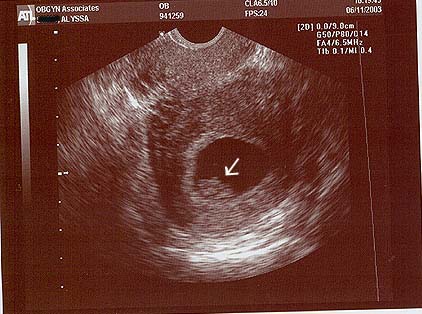

| Since my blood test was positive, they wanted me to come in for a sonogram to see what was going on, and see if everything was normal. I went in for that on Wednesday, June 4th. Sure enough, there was the sac and this time there was a little form inside it - with a little tiny heart beating away! I was in shock, the ultrasound tech kept asking if I was going to be alright. I still wasn't sure how to feel - this was truly a miracle, I'd pictured months of fertility treatments coming our way. But since my fertility doctor didn't have anything to do with the pregnancy this time, my insurance wanted me to go back to my regular ob/gyn. I scheduled an appointment with them for June 11th. She also wanted to do a sono, to check things out, and it looked good and the dates seemed correct. My first doctor's office estimated conception around May 1st, with a due date of January 22nd, 2004. Here's the picture from that appointment, it's the blob where the arrow is pointing - cute, huh? I've nicknamed the baby "Pudge", since that's what it's doing to my stomach!! |